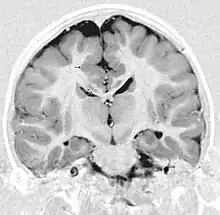

Gray matter heterotopia is a neurological disorder caused by gray matter being located in an atypical location in the brain.[1]

Detection of heterotopia generally occurs when a patient receives brain imaging—usually an MRI or CT scan—to diagnose seizures that are resistant to medication. Correct diagnosis requires a high degree of radiological skill, due to the heterotopia's resemblance to other masses in the brain.